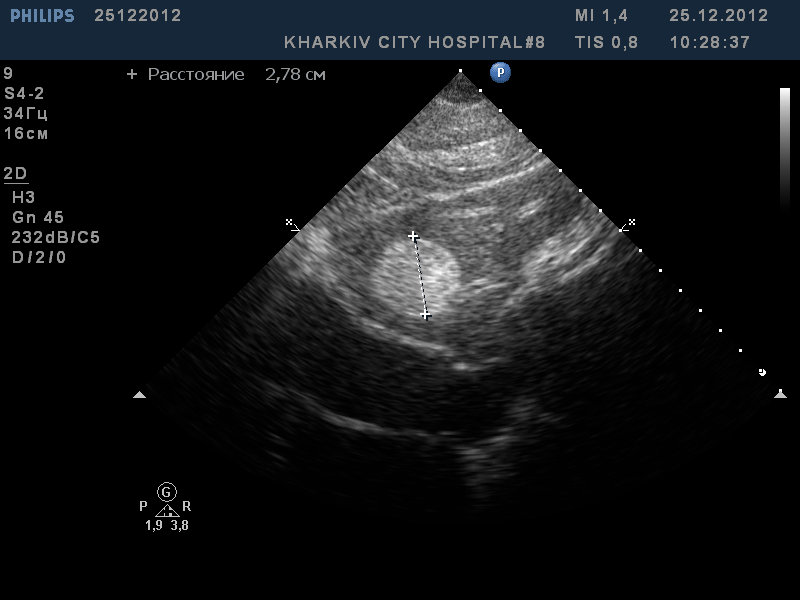

Пациентка 74года. гипертоник, сильная одышка при ходьбе, мерцательная аритмия.

Интересный момент- щеки пациентки темновато красные- напоминает при митральном стенозе. При обследовании стало ясно почему.

Имеется в полости левого предсердия флотирующая в кровотоке миксома, размерами до 4,3см.

Миксома левого предсердия оказалась тромбом

Докладываю. Оказалось таки тромб)))) Коллеги кардиохирурги пересмотрели на чреспищеводном и увмдели что прикреплена, так сказать, к ушку ЛП.

решили провести антикоагулянтую терапию. " Миксома" растворилась в тумане)

Да, трудное это дело дифдиагноз тромба и миксомы.